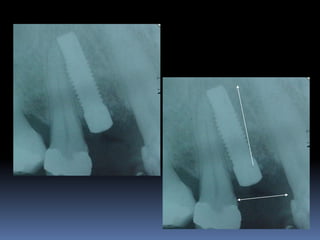

Guia radiográfico

-posição ótima do implante com marcadores

radiopacos

•Facilita perfuração, paralelismo e distribuição dos

implantes

•Elimina a medição entre implantes

•Permite alternar as possibilidades de instalação